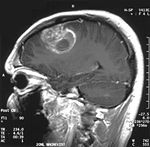

Глиальная опухоль высокой степени злокачественности, глиома головного мозга.

Это одна из форм опухолей центральной-нервной системы, возникающая из глиальных клеток, входящих в состав нервной ткани и выполняющих функцию в росте нейронов. Аномальное деление клеток формирует новообразование, которое в случае с глиобластомой характеризуется интенсивным, агрессивным течением и быстрым распространением. Опухоль проникает в здоровые ткани метастазами и не имеет четких границ, что затрудняет ее хирургическое удаление. Провоцирующими ее развитие факторами называют генетические заболевания, сбой в гормональной системе, воздействие радиации, канцерогенов, вирусов. Глиобластома может возникнуть в любом отделе головного мозга.